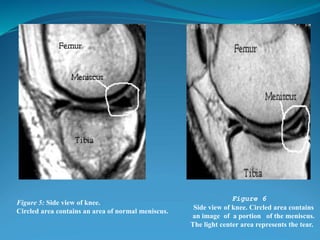

Figure 5: Side view of knee.

Circled area contains an area of normal meniscus.

Figure 6

Side view of knee. Circled area contains

an image of a portion of the meniscus.

The light center area represents the tear.